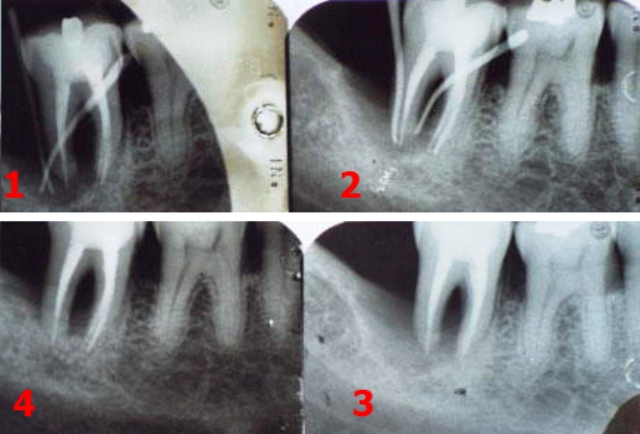

piorrea